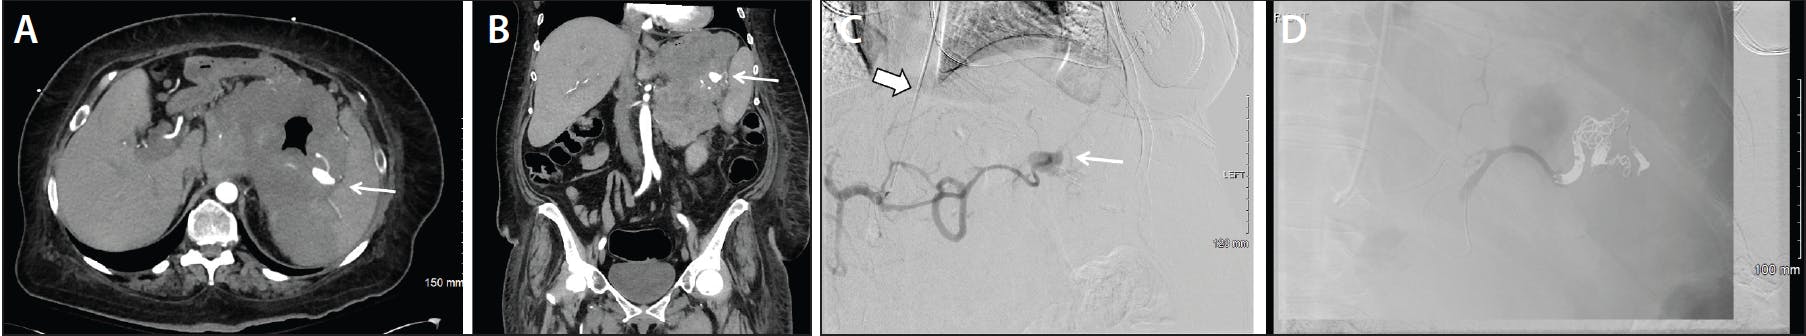

Figure 1. A man in his mid 60s presented with decompensated cirrhosis with abdominal wall pain and swelling associated with a 4-g hemoglobin drop (10 to 6 g) and new tachycardia after paracentesis. Two units of packed red blood cells (PRBCs) were given and interventional radiology consulted. CT without contrast (acute kidney injury on stage 4a chronic kidney disease) demonstrating a left abdominal wall hematoma with mixed density, suggesting acute hemorrhage (A). Digital subtraction angiography (DSA) of the external iliac artery with a 5-F Vert catheter (thick arrow) via right radial access demonstrating a pseudoaneurysm from the branch of the left inferior epigastric artery (thin arrow) (B). Coil embolization across the culprit branch containing the pseudoaneurysm (C). Hemoglobin stabilized postprocedure without further transfusion.